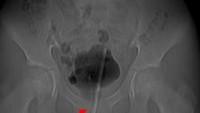

Diprediksi ada sekitar 800 jarum 'susuk' yang bersarang di tubuh wanita ini. Radiografi perut dari pasien yang sama menunjukkan jarum berada paling banyak di area panggul. (Foto: Journal of Radiology Case Reports)

Diprediksi ada sekitar 800 jarum susuk yang bersarang di tubuh wanita ini. Radiografi perut dari pasien yang sama menunjukkan jarum berada paling banyak di area panggul. (Foto: Journal of Radiology Case Reports)